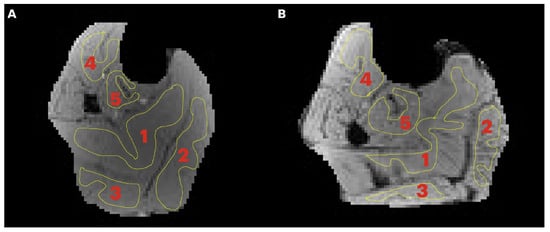

Region of interest analysis: A region of interest was manually positioned in each of five calf muscles: medial gastrocnemius (MG), lateral gastrocnemius (LG), soleus (SOL), tibialis posterior (TP), and tibialis anterior (TA) (Figure 1). Care was taken to avoid low- and high-intensity regions within muscle as well as the edges of the muscle. Low-intensity regions were either fat (since the images were acquired with fat suppressed) or fascicles (connective tissue) while high-intensity areas potentially correspond to blood vessels. Parametric images were computed for all the MT indices evaluated in the current paper; however, the quantitative indices were computed from the average signal intensity in the muscle ROIs (Figure 1) extracted from the acquired images.

Figure 1. Transverse image of the lower leg of a young (A) and senior (B) subject with typical regions of interest manually contoured in the soleus (1), medial gastrocnemius, MG (2), lateral gastrocnemius, LG (3), tibialis anterior, TA (4), and tibialis posterior, TP (5). Care was taken to limit the ROI to the inside of the muscle borders and to avoid major fascicles.